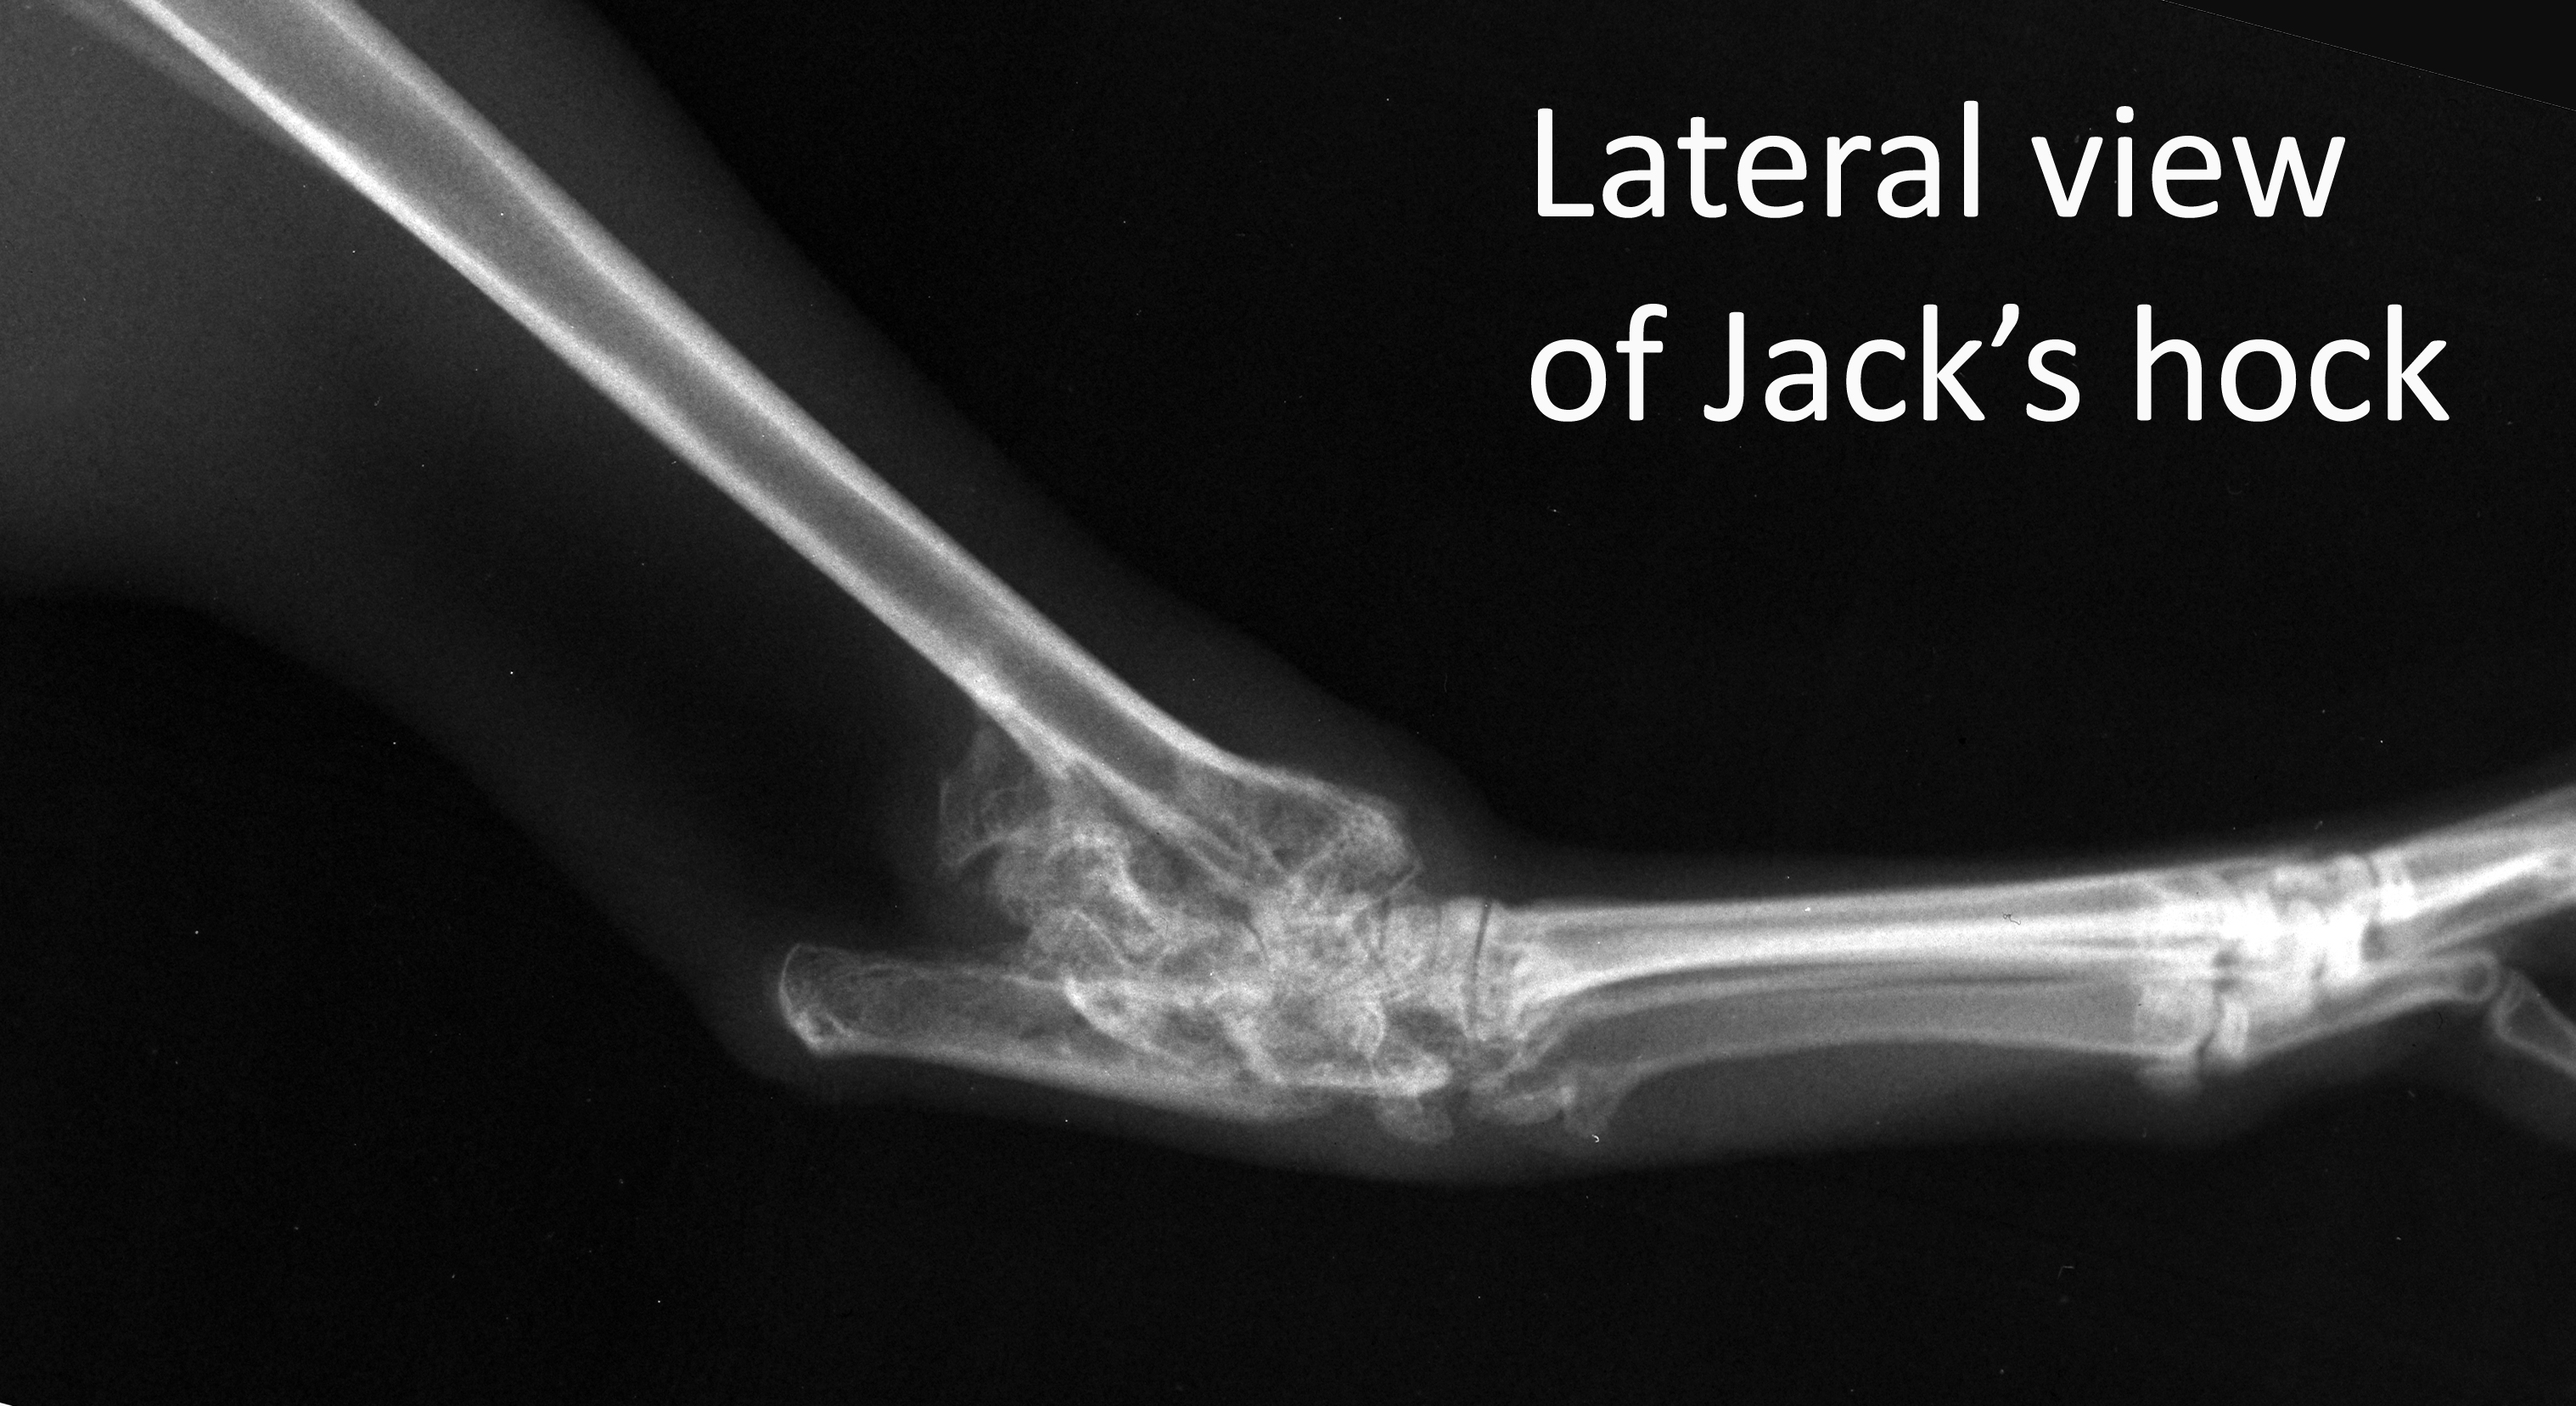

Jack's hock

Labelled image of Jack's hock lateral

Radiograph

Orthopaedics

Jack